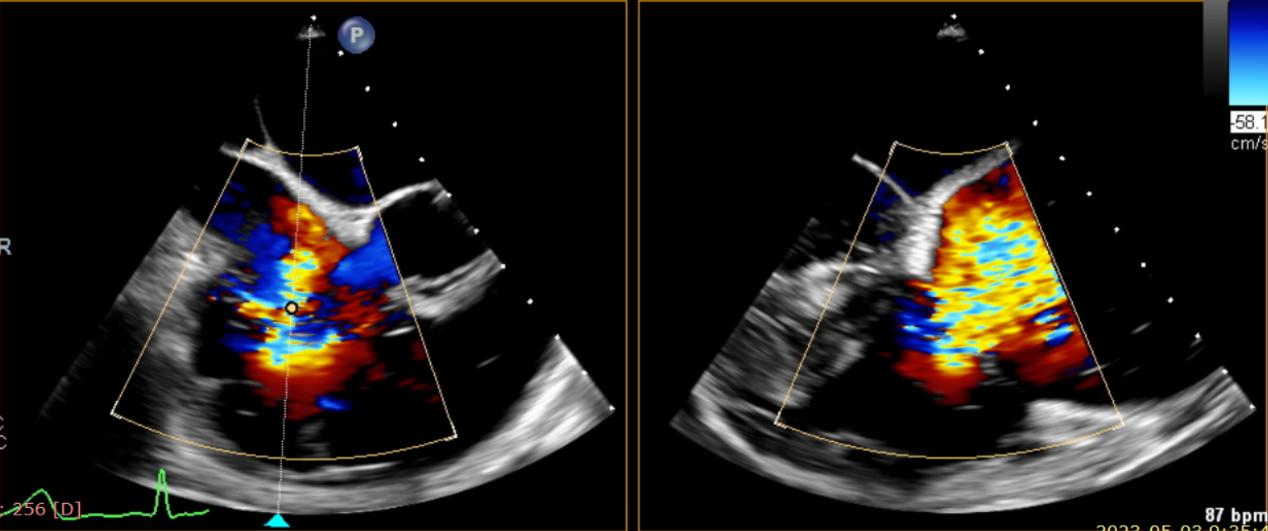

術前超聲提示大量三尖瓣反流

術中輸送器在超聲引導下調整位置

術后超聲提示無瓣周漏